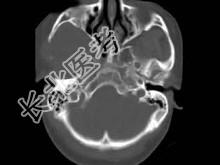

- 单项选择题男,30岁, 感右下颌部有一肿物,逐渐肿大, 胀痛,局部麻木1月余, 结合图像,最可能的诊断是 ( )

A、神经纤维瘤

B、神经鞘瘤

C、血管瘤

D、下颌骨肉瘤

E、软骨瘤